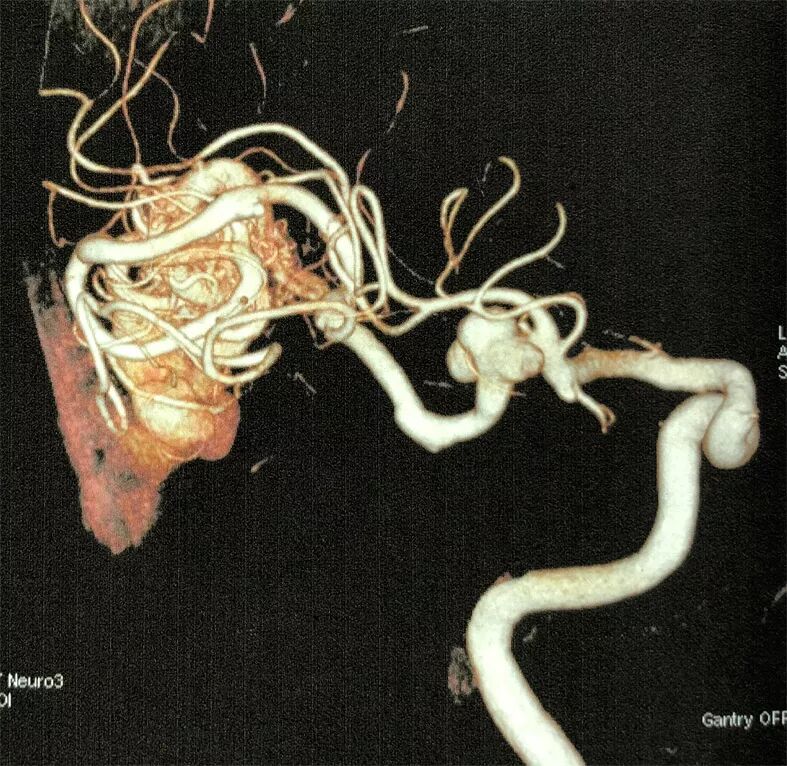

2. 术前DSA示:右侧大脑中动脉主供血AVM,向横窦乙状窦引流,合并多发血流相关性动脉瘤。

术后CTA见血管畸形切除完全,IIa动脉瘤夹闭完全

本文报道病例未破裂的AVM合并供血动脉血流相关性动脉瘤,按Redekop分类,本例患者AVM同时伴发供血动脉近端(IIa)及供血动脉远端(IIb)动脉瘤。我们首选在电生理监测下,控制AVM供血的大脑中动脉,采用无出血手术操作技术,沿AVM和周边脑组织分界的胶质增生带分离完整切除AVM。对于伴发的供血动脉血流相关性IIa和IIb动脉瘤采用不同的策略。近端IIa动脉瘤一期显微夹闭处理,远端IIb动脉瘤随访观察的处理策略。手术顺利,术后病人恢复良好,没有功能障碍。